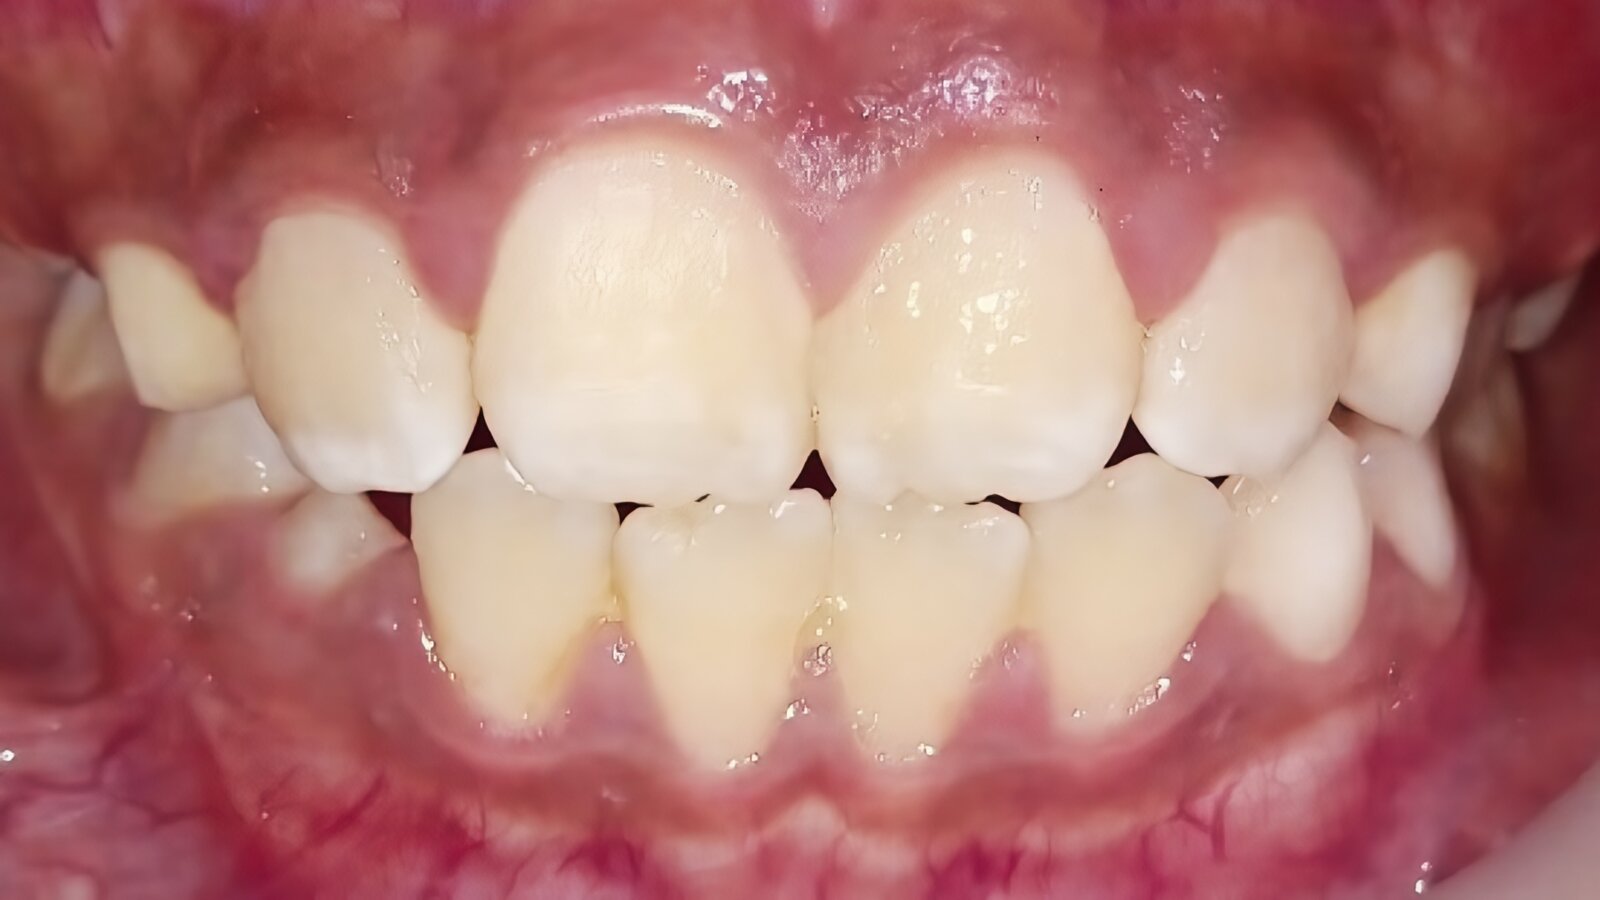

Figura 4. A) Paciente de 18 años con condiciones prístinas de periodonto, línea roja (LR) sin alteración. Paciente de 50 años con colapso simétrico severo total e incongruencia de la arquitectura en la LR. Estadio 4 de la clasificación periodontal de la PPA/ FPA, 2017.